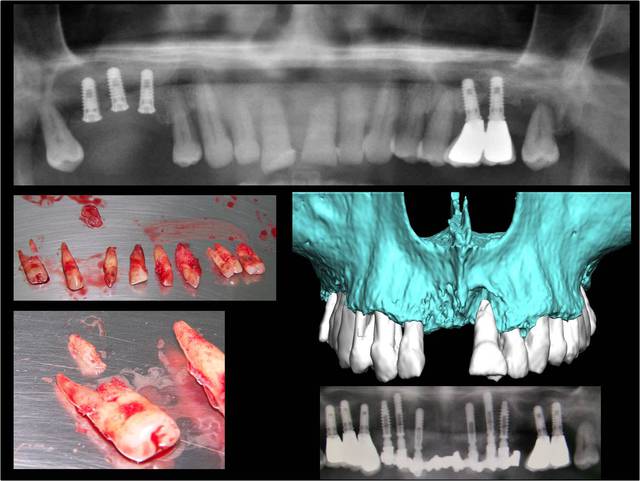

Wilson, sur l’image jointe il y a l’OTP pré- opératoire, les dents extraites, une modélisation 3D du site et l’OTP post-opératoire avec les implants et prothèses posée en 1 temps chirurgical.

Quel aurait été ton plan de traitement ?

Que reproches-tu au résultat post-opératoire ?